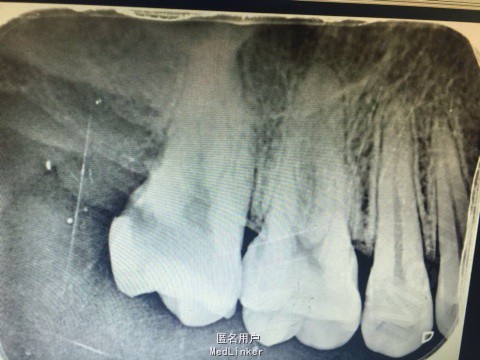

主诉:患者右上后牙冷热刺激痛数日。 病史:数日来,患者右上后牙冷热刺激疼痛不适,偶有自发痛影响进食,来院就诊。

查体:17远中颈部龋坏,探(+),冷热诊疼痛明显且持续较长时间。叩(-),X线示17远中颈部龋坏深达牙髓腔。

诊断:17深龋伴牙髓炎 治疗: 局麻下17去腐,开髓揭髓顶降牙合,冲洗髓腔,拔髓疏通根管,测量根管镍钛器械进行根管预备,低浓度次氯酸钠进行根管的冲洗化学预备,拭干根管,进行根管试尖,X线示恰充,进行热牙胶垂直加压连续波充填法进行根管充填。暂封进行嵌体修复。